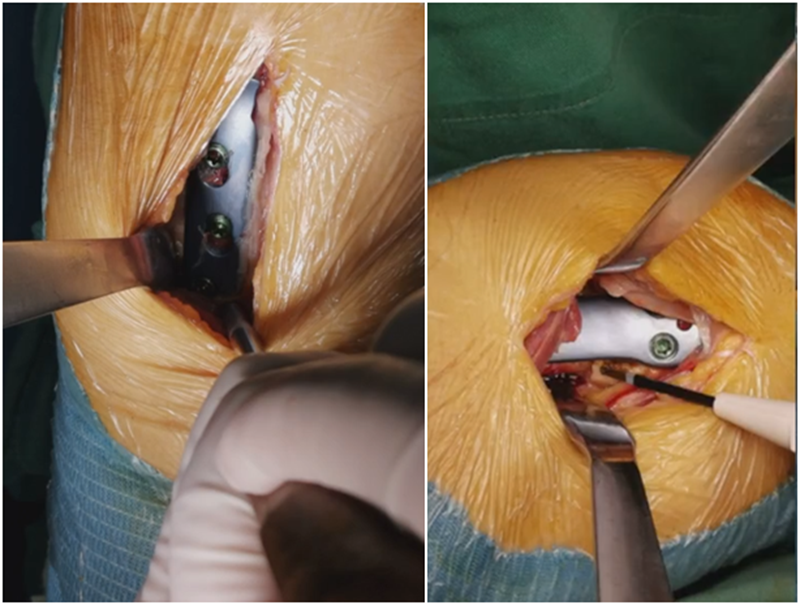

术中发现螺钉松动,截骨端出现坎插迹象。

近端螺钉松开,调整力线,重新固定后,在外侧加小钢板抗旋。